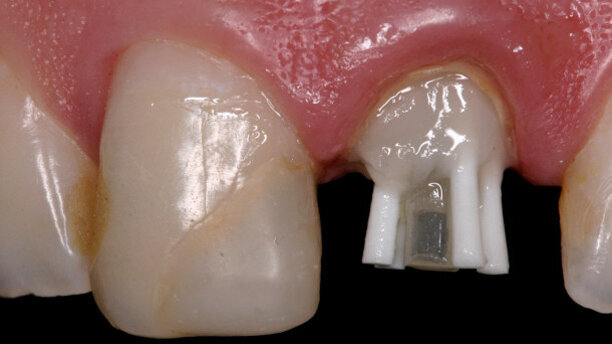

First, the decayed tissue was removed from the remaining tooth structure and the fibreglass pin was selected (Exacto # 3, Angelus), as well as the accessory pins (Reforpin, Angelus; Fig. 4). The radicular conduit was isolated with mineral oil and the compound resin was applied (Fill Magic NT Premium, Vigodent/COLTENE) over the remaining tooth (Figs. 5 & 6) with the aid of a #1/2 Suprafill spatula (SS White). After filling of the conduit with resin, the Exacto pin and the pre-silanised accessory pins (Silano, Angelus) were inserted with the application of an adhesive (Fusion-Duralink, Angelus; Figs. 7–9). Next, the initial photoactivation was conducted on the pin and resin for 20 seconds.

Finally, the coronal reconstruction was performed with the previously used compound resin in incremental portions and photoactivation was conducted (Figs. 10 & 11). A marking was made on the most incisal portion of the pins to guide the subsequent cropping of the pins (Fig. 12). The anatomical pin was then removed and the final photoactivation was performed for 40 seconds (Fig. 13). Soon after, the pin was adapted to the remaining coronal structure (Fig. 14).